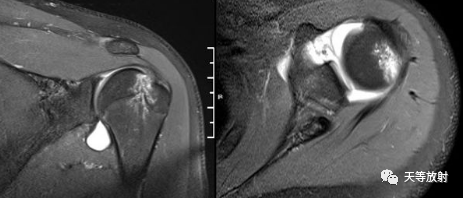

Hill-Sachs损伤

Hill-Sachs损伤:肩关节前脱位时,肱骨头撞向关节盂缘可导致肱骨头的后外侧的嵌插骨折

MR间接关节造影1.5T轴位T1W脂肪抑制

MR间接关节造影1.5T冠状面T1W脂肪抑制

Hill-sachs,Bankart,关节囊损伤